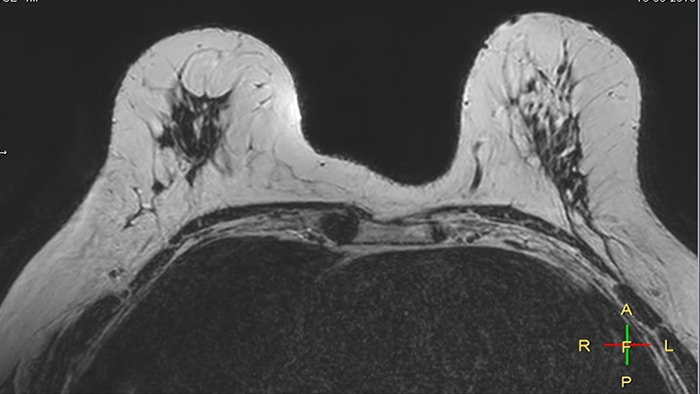

Compressed SENSE 3:54 min

Compressed SENSE, scan time 3:54 min

C-SENSE factor 12

Voxels acq 0.8 x 0.72 x 1.8 mm

Voxels recon 0.63 x 0.63 x 0.9 mm

SENSE 6:32 min

SENSE, scan time 6:32 min

SENSE factor 3

Voxels acq 0.8 x 0.8 x 1.8 mm

The time gain with Compressed SENSE was also used to increase resolution in order to help radiologists identify the tumor characteristics more confidently which may be used for a more personalized treatment. For example, in breast imaging, resolution is crucial for visualization of very small lesions. Compressed SENSE allows to scan thinner slices, allowing a 3D isotropic sequence which can provide increased diagnostic confidence for the radiologists.